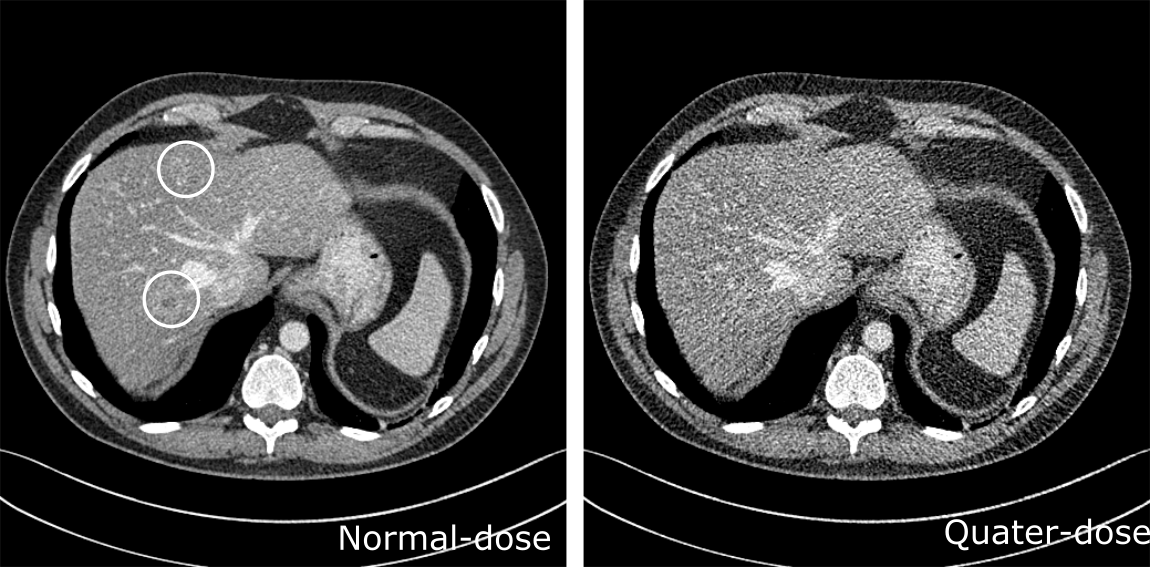

A slice that contained metastasis is selected to demonstrate the image quality improvement with cascaded CNNs visually. Figure 5 showed the corresponding normal-dose and original low-dose image of the selected slice, where the two metastasis contained in the slice were marked with white circles. The denoised results and corresponding 70% blended images are shown in Figure 6. Compared to the low-dose image, the visibility of the metastasis, especially the one near the chest, is greatly improved. There were noticeable blocky artifacts in CNN5-1 results in the liver, but it was greatly reduced by applying CNN cascades and almost gone in the results of CNN5-8. For the blended results, the improvement was not obvious as that on the original ones because of the increased noise level. Compared to CNN5-1, the cascaded CNNs gave more uniform liver areas with less speckles. No useful information lost such as blurring was observed with increased number of cascades.